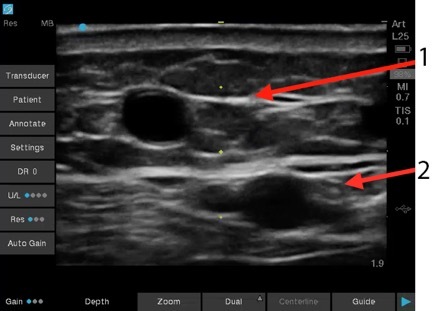

Dialysis AV Fistula versus Artery Image

AV Fistula

Artery